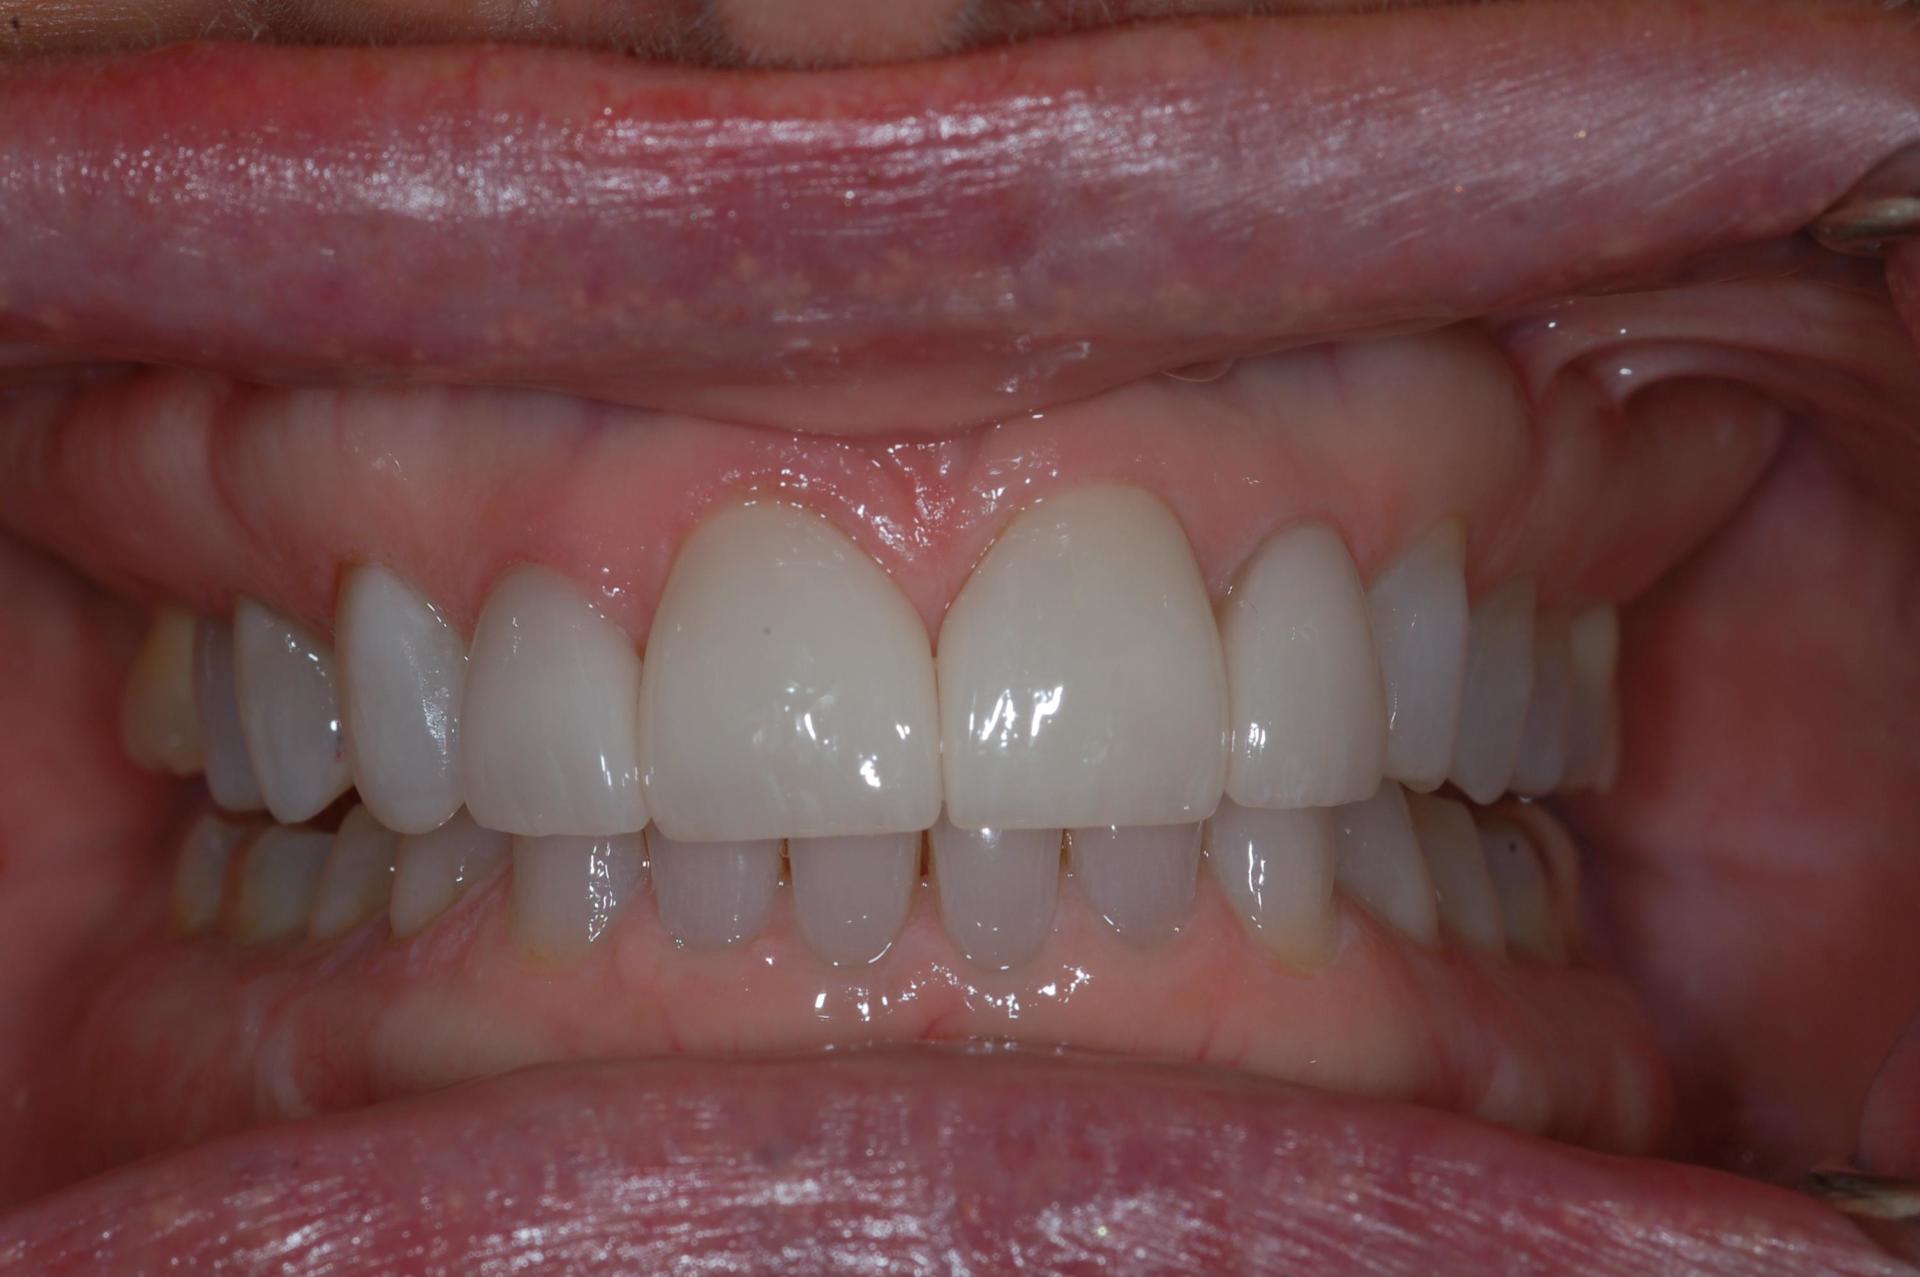

Resin Bonded Restorations (Composites)

This case illustrate a minor touch up with resin bonding. This is an alternative option when the patient does not want extensive treatment. One visit and no

anesthetic!